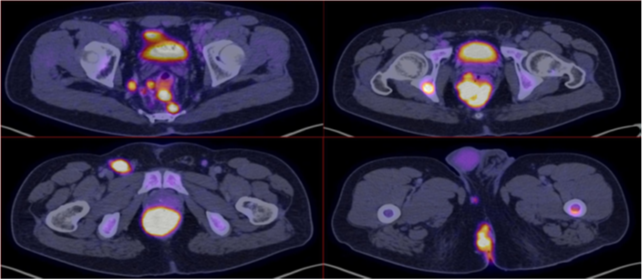

Positron Emission Tomography (PET-CT) was performed with evidence of tumor hypermetabolic activity at the rectal level (SUVmax 70.2), presacral and pararectal lymph nodes (SUVmax 46.6), inguinal (SUVmax 52.3), ischium, ischiopubic ramus (SUVmax 43.3), Liver (SUVmax 8.4). (Figure 2 &3)

Figure 2 E: Sagittal reconstruction of PET-CT with evidence of tumor hypermetabolic activity at the rectal level (SUVmax 70.2) FIGURES F and G: PET-CT coronal reconstruction with evidence of tumor metabolic activity at the rectal level (SUVmax of 70.2), ischium and femurs (SUVmax of 43.3).

Figure 3 Axial reconstruction with evidence of tumor hypermetabolic activity at the rectal level (SUVmax 70.2), presacral and pararectal lymphadenopathies (SUVmax 46.6), inguinal (SUVmax 52.3).